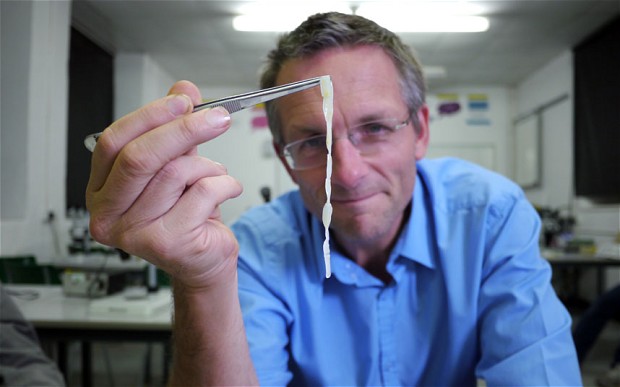

El presentador de la BBC, el doctor Michael Mosley, se autoinfectó con parásitos con el propósito de conocer con detalles de cómo actúan estos dentro del cuerpo humano.

Para la realización de este documental, llamado “Viviendo con parásitos“, tuvo que tragar tres larvas de tenia, un gusano que puede llegar a crecer hasta los 10 metros de longitud y que se transmite comiendo carne infectada de vaca.

Semanas después de ingerir las larvas, introdujo a su sistema una cámara píldora para obtener capturas de lo que ocurría en su cuerpo. Las imágenes, a las que accedió a través de su iPad, mostraron un gusano de más de un metro de largo viviendo en su intestino grueso.